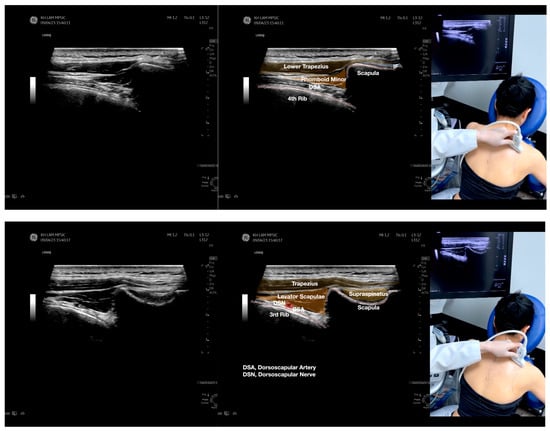

Figure 2.

Sonoanatomy of the lateral border of the inferior trapezius, its related muscles, and the infraspinatus fascia. The step-by-step scanning techniques of the structures illustrated in this figure have been shown in Video S6. Available online: https://www.dropbox.com/s/vjj49wiwdsidouz/Figure%202.docx?dl=0 (accessed on 1 January 2023). Dynamic ultrasound scanning of the anterior shoulder with the humerus externally rotated (palm up), elbow straight, and the shoulder actively flexed and abducted at about 90 to 100 degrees shows that the fibrotic and thickened bursa was noted to be snapping between the subscapularis tendon and the coracoacromial ligament, as shown in Video S3. The patient noticed this snapping during many of his daily activities with his shoulder flexed just above 90 degrees, e.g., taking off clothes and combing hair. Ultrasound-guided injection of the thickened and fibrotic bursa did not reproduce the usual pain nor reduce the pain, and it did not improve the shoulder snapping and flexion power with the elbow straight, shoulder flexed to 90°, and the humerus externally rotated (palm up). Ultrasound-guided injection of the cortical break reproduced the concordant pain and temporarily and partially reduced the pain with snapping and residual anterior shoulder pain (Video S4), but it did not change the snapping or weakness in the right shoulder flexion with the humerus in external rotation. With the failure of direct anterior treatment to the suspected lesions, it was essential to further explore other causes for the anterior painful snapping. Further detailed musculoskeletal examination of the scapular movement showed that the right scapulothoracic movements were not smooth compared to the left counterpart (Video S5) [4,5]. There might be some disruptions in the right infraspinatus fascia (IF) and its related muscles, including the lateral edge of the right inferior trapezius, rhomboid minor and major [6], teres major, latissimus dorsi [7,8] (LD), and posterior deltoid attachments to the IF [9,10]. Clinically, prominent and active trigger points were observed in the right infraspinatus muscle. Holding the inferior angle of the scapula, with the examiner’s fingers, especially over the origin of the teres major muscle over the scapula, the latissimus dorsi [11,12,13] and the scapular insertion of the rhomboid major muscle significantly improved the power of the resisted shoulder flexion with the elbow straight and the shoulder flexed to 90° with the humerus externally rotated (palm up). In order to illustrate the utilization of ultrasound-guided sonopalpation and ultrasound-guided digital palpation for detecting the suspected lesions of the IF and its related muscles, we presented the following videos (Videos S6–S9) and still images (Figure 2, Figure 3, Figure 4 and Figure 5) to demonstrate the essential techniques and crucial points of getting the normal sonoanatomy of the IF and its related structures. The gross anatomy of the IF and its related muscles were also shown in Figure 6, Figure 7 and Figure 8.